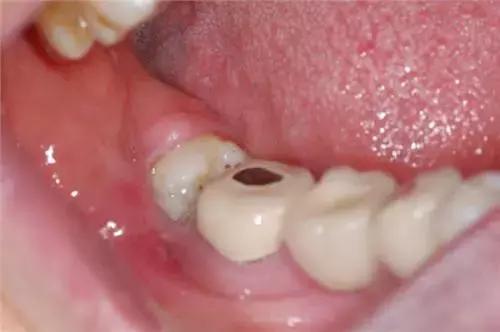

1、 由于萌出不全,后侧的牙龈覆盖,其部分牙冠形成冠周袋积存食物和细菌,可以造成局部软组织经常发炎,疼痛难忍,甚至导致张口受限而进食困难。

智齿牙冠周围的软组织发生炎症,主要症状就是肿胀疼痛。所以,大家一定在智齿开始疼痛时就要注意预防冠周炎,及早诊断拔除,千万不要拖延不治!